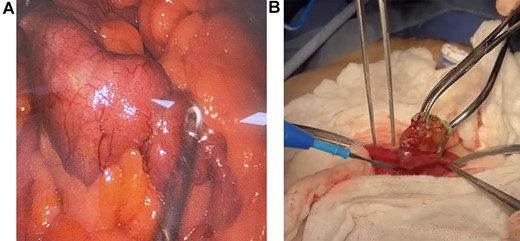

On laparoscopy, the full extent of the bowel was dilated, and the foreign body was discovered 1.80 m proximal to the ileocecal valve; then, the bowel was grasped and extracted through the umbilical port. After placing a skin protector, a 3-cm longitudinal incision on the antimesenteric side of the bowel was done, the foreign object was extracted, and the enterotomy was closed in a transverse fashion in two layers. No perforation, necrosis, or free fluid was found, and the remainder of the procedure was completed without complications (Fig. 2A and 2B).

(A) Laparoscopy, the foreign body is found in the bowel. (B) Extraction of the foreign body through enterotomy.